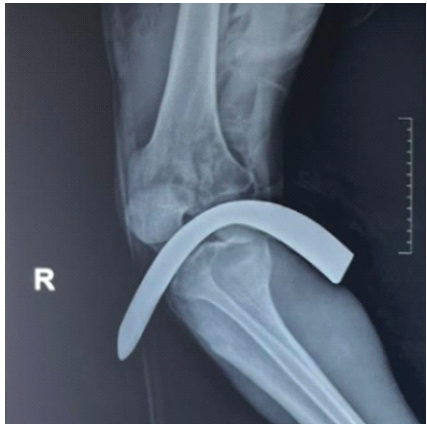

After ensuring intravenous access and adequate analgesia, the patient party was counseled and prognosticated. He was administered tetanus prophylaxis and intravenous antibiotics. Now, attention was given to the wounds. All wounds were first washed with copious amount of normal saline. The visible ends of the two large metallic objects passing through the knee and ankle joints were also gently cleaned of all visible darts with saline and antiseptic solutions. Any fracture of the adjoining bones is quickly ruled out by doing X-ray examinations. Vascular Doppler study of the affected limb showed good biphasic flow in the dorsalis pedis and posterior tibial arteries. Angiogram was not advised by the vascular surgeon. Routine blood investigations, including blood grouping and cross-matching were sent as emergent, and the patient was planned for emergency surgery (Figs. 4 and 5).

Figure 4: X-ray of the knee joint with the metal rotavator blade in situ.

Figure 5: X-ray of the ankle joint showing the rotavator blade in situ.